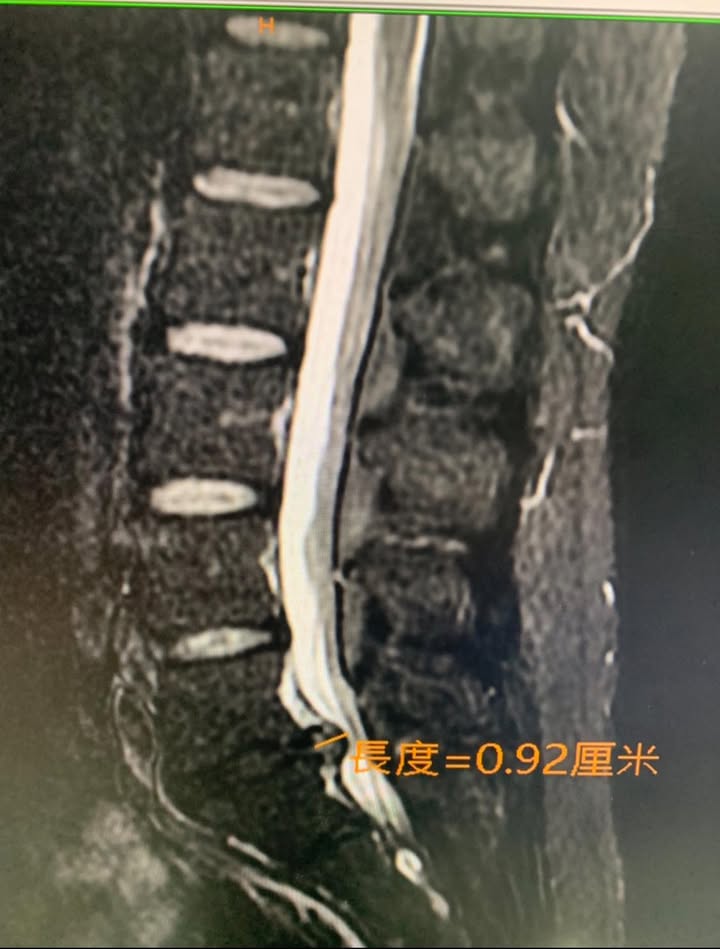

Cervical Spine Treatment Cases 腰椎治療案例 #腰椎明顯滑脫醫案 #感謝三重蔡先生熱情見證 #曾經大痛到無法工作跟無法睡覺 #脊椎整... 2020.03.07 #感謝雲林李阿姨熱情見證 #腰椎滑脫合併椎管狹窄 #脊椎整合中醫微創療法逆轉勝 2020.03.01 曾經腰痛連大腿小腿到無法睡覺 大醫院核磁共振檢查後證實椎間盤突出 四個多月的疼痛原... 2020.03.05 #跨國治療台灣醫療奇蹟 #遠從澳洲坐飛機回台專門接受治療 #台灣中醫脊椎整合微創療法... 2020.01.17 #兒子老婆陪同林伯伯一起見證奇蹟 #腰椎滑脫合併椎管狹窄 #治療前走路無法超過五分鐘 ... 2019.12.28 #跨國治療台灣醫療奇蹟 #遠從越南坐飛機專門接受治療 #台灣中醫脊椎整合微創療法立大... 2019.12.26 再度逆轉勝!腰椎治療醫案 原本痛到懷疑人生都想去手術了 八週治療後生路活虎!還可以... 2019.12.18 #腰痛一年原本打算去開刀 #逆轉勝大幅度改善 #脊椎整合中醫微創療法 2019.12.14 #感謝南投草屯簡阿姨熱情見證 #腰椎滑脫合併椎管狹窄與脊椎側彎的超難患者出現 #超級... 2019.12.04 #同時椎間盤突出又輕微腰椎滑脫 #大痛到每天早上都無法起床跟刷牙 #腰痛的日子是黑白... 2019.12.01 🆕聚焦「薦髂關節障礙」 #非典型下背痛醫案 #核磁共振有突出卻復健效果不好 #感謝新竹... 2019.11.18 #經典椎間盤突出醫案 #再度逆轉勝原本考慮開刀 #感謝患者熱情見證 #脊椎整合中醫療法... 2019.11.01 #腰痛連大腿快一年 #曾經痛到無法走路是怎麼回事 #椎間盤突出就是那麼痛 #除了開刀之... 2019.10.22 #腰椎整合中醫微創療法逆轉勝 #長達半年多無法平躺睡覺 #坐骨神經痛就是那們痛 #原本... 2019.10.12 #腰椎間盤突出脫垂壓迫神經根醫案 #屁股痛連大腿是怎麼回事 #脊椎整合中醫微創療法 #... 2019.10.08 ← 上一頁 12 13 14 15 16 下一頁 →